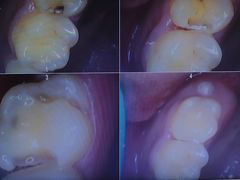

• 牙博士口腔品牌连锁(杨浦店)

• -牙博士口腔品牌连锁(杨浦店)